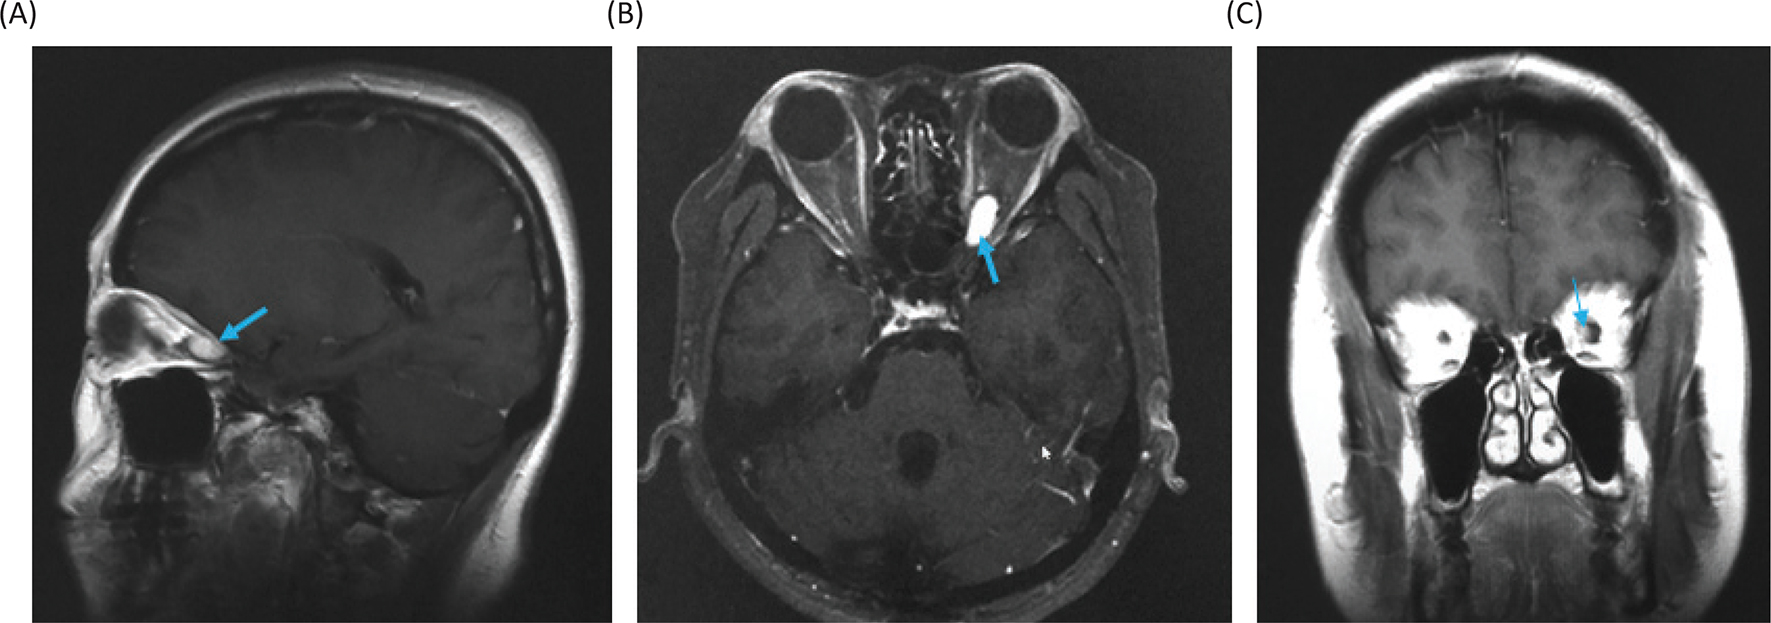

Magnetic resonance imaging (MRI) of the head showed a Gd-enhanced well-circumscribed mass on the left retrobulbar optic nerve in the orbital, and three-dimensional MRI showed the tumor enveloped the left optic nerve (Figure 4).

Fig 4

Figure 4. Magnetic resonance images before radiosurgery. (A) Gadolinium (Gd)-enhanced T1-weighted image, sagittal. (B) Gd-enhanced T1-weighted image, axial. (C) Gd-enhanced T1-weighted image, coronal. Yellow arrows show the tumor. (D) Three-dimensional planning MRI for radiosurgery. The light blue color indicates the tumor enveloping the optic nerve.

Figure 5. Gadolinium-enhanced magnetic resonance images at 18 months after the stereotactic radiosurgery. (A) Sagittal image. (B) Axial image. (C) Coronal image.